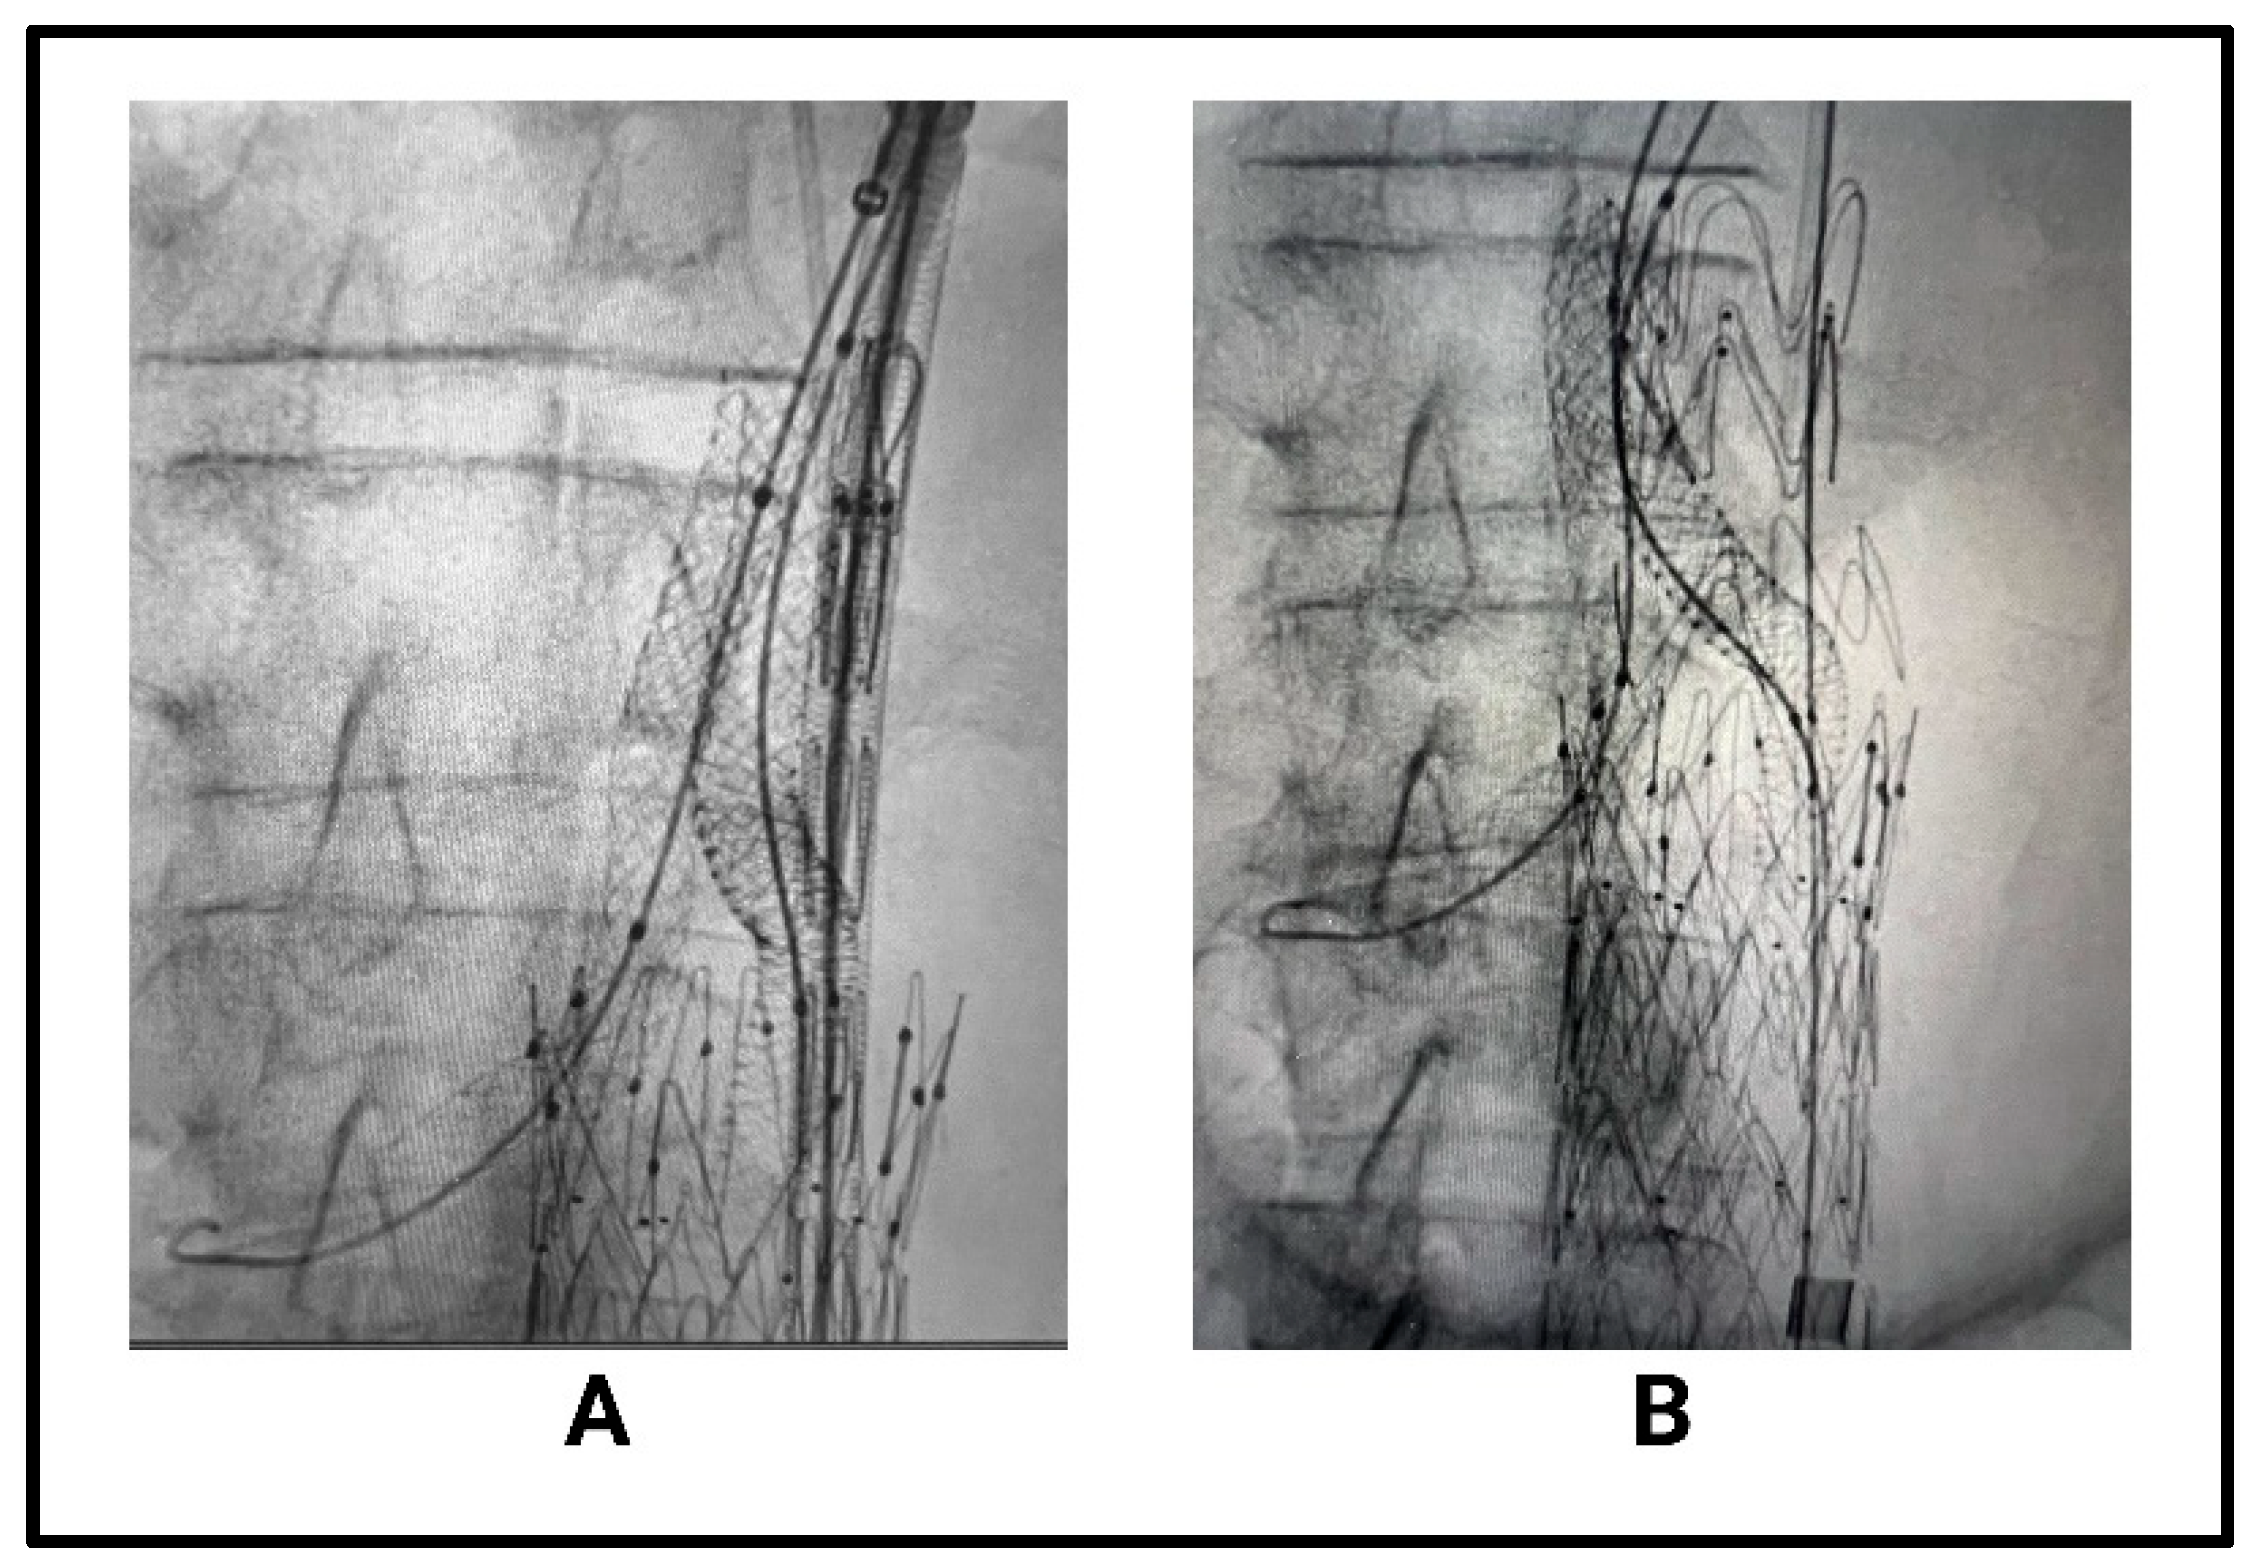

2.2.3. Chimney EVAR (ChEVAR) and Periscope Techniques

- Kopp, R.; Stachowski, L.; Puippe, G.; Zimmermann, A.; Menges, A. Long-Term Outcomes of Endovascular Aortic Repair with Parallel Chimney or Periscope Stent Grafts for Ruptured Complex Abdominal Aortic Aneurysms. J. Clin. Med. 2025, 14, 234. [Google Scholar] [CrossRef] [PubMed]

- Jennings, J.; Sheahan, L.; Gloss, C.; Vogel, T.; Bath, J. Multiple Chimney Endografts (ChEVAR) for Ruptured Pararenal Aortic Aneurysm. Ann. Vasc. Surg. 2021, 75, 531.e1–531.e6. [Google Scholar] [CrossRef]

- Jernigan, E.G.; Nguyen Tran, N.; Qato, K.; Giangola, G.; Carroccio, A.; Conway, A.M. Outcomes of chimney/snorkel endovascular repair for symptomatic and ruptured abdominal aortic aneurysms. J. Vasc. Surg. 2021, 74, 1117–1124. [Google Scholar] [CrossRef]

- Touma, J.; Caradu, C.; Sylvestre, R.; Settembre, N.; Schneider, F.; Moia, A.; Ahmed, B.; Lebas, B.; Gaudric, J.; Alsac, J.; et al. Multicentre Experience with the Chimney Technique for Abdominal Aortic Aneurysms in French University Hospitals. Eur. J. Vasc. Endovasc. Surg. 2020, 59, 776–784. [Google Scholar] [CrossRef]

- Lindblad, B.; Jabr, A.; Holst, J.; Malina, M. Chimney Grafts in Aortic Stent Grafting: Hazardous or Useful Technique? Systematic Review of Current Data. Eur. J. Vasc. Endovasc. Surg. 2015, 50, 722–731. [Google Scholar] [CrossRef]